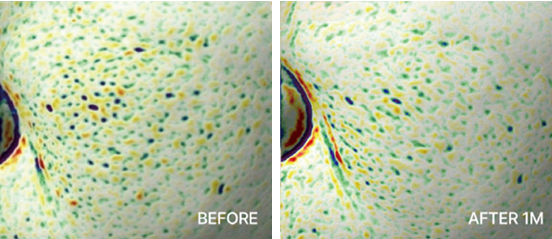

탄력 개선

탄력 개선